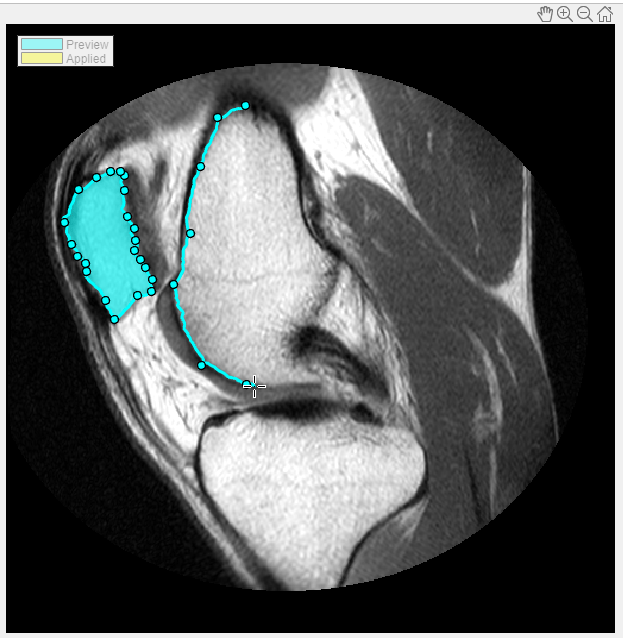

Select the type of ROI you want to draw. For this example, choose Assisted Freehand. As you move the cursor over the image, it changes to the crosshairs shape. Press the mouse button, and begin drawing a freehand shape over the area of the image that you want to segment. With the Assisted Freehand ROI option, which is preselected, you can draw a freehand shape that automatically follows edges in the underlying image to help you draw a more accurate ROI. As you draw, click the mouse to create waypoints. Waypoints can help you make fine adjustments to the shape after you finish drawing. To add additional waypoints after you finish drawing, double-click on the ROI edge.

Continue drawing shapes until all the areas you want to segment are identified. To save the regions your have drawn, click Apply (their color changes to yellow). To return to the Segmentation tab, click Close ROI.